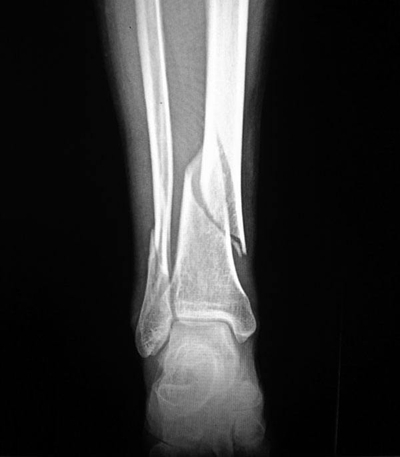

骨折圖片

A:腓骨是人體中小腿骨中比較細的一根骨骼,它的負重比較少,一般腓骨近端的骨折都伴有脛骨的骨折,也可能伴有踝關節的骨折。單純的腓骨近端骨折一般不需要手術,腓骨的近端有腓總神經纏繞,離腓總神經非常的近,所以如果手術的話很容易損傷腓總神經,造成足下垂……